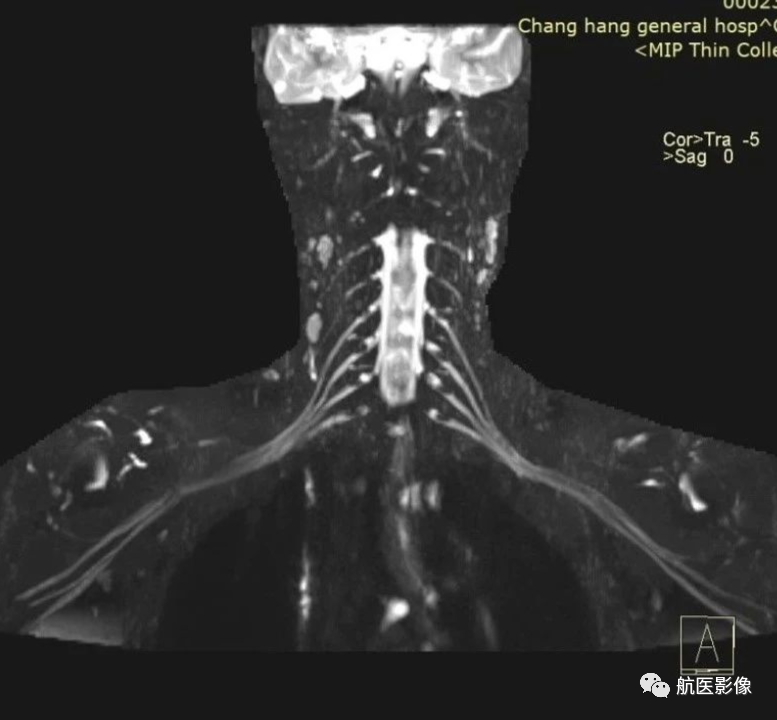

6. MR周围神经成像:

评估臂丛或腰骶丛的病变,如神经卡压综合征、血肿或肿瘤压迫神经、神经损伤等。

磁共振臂丛神经成像

MR腰骶丛成像